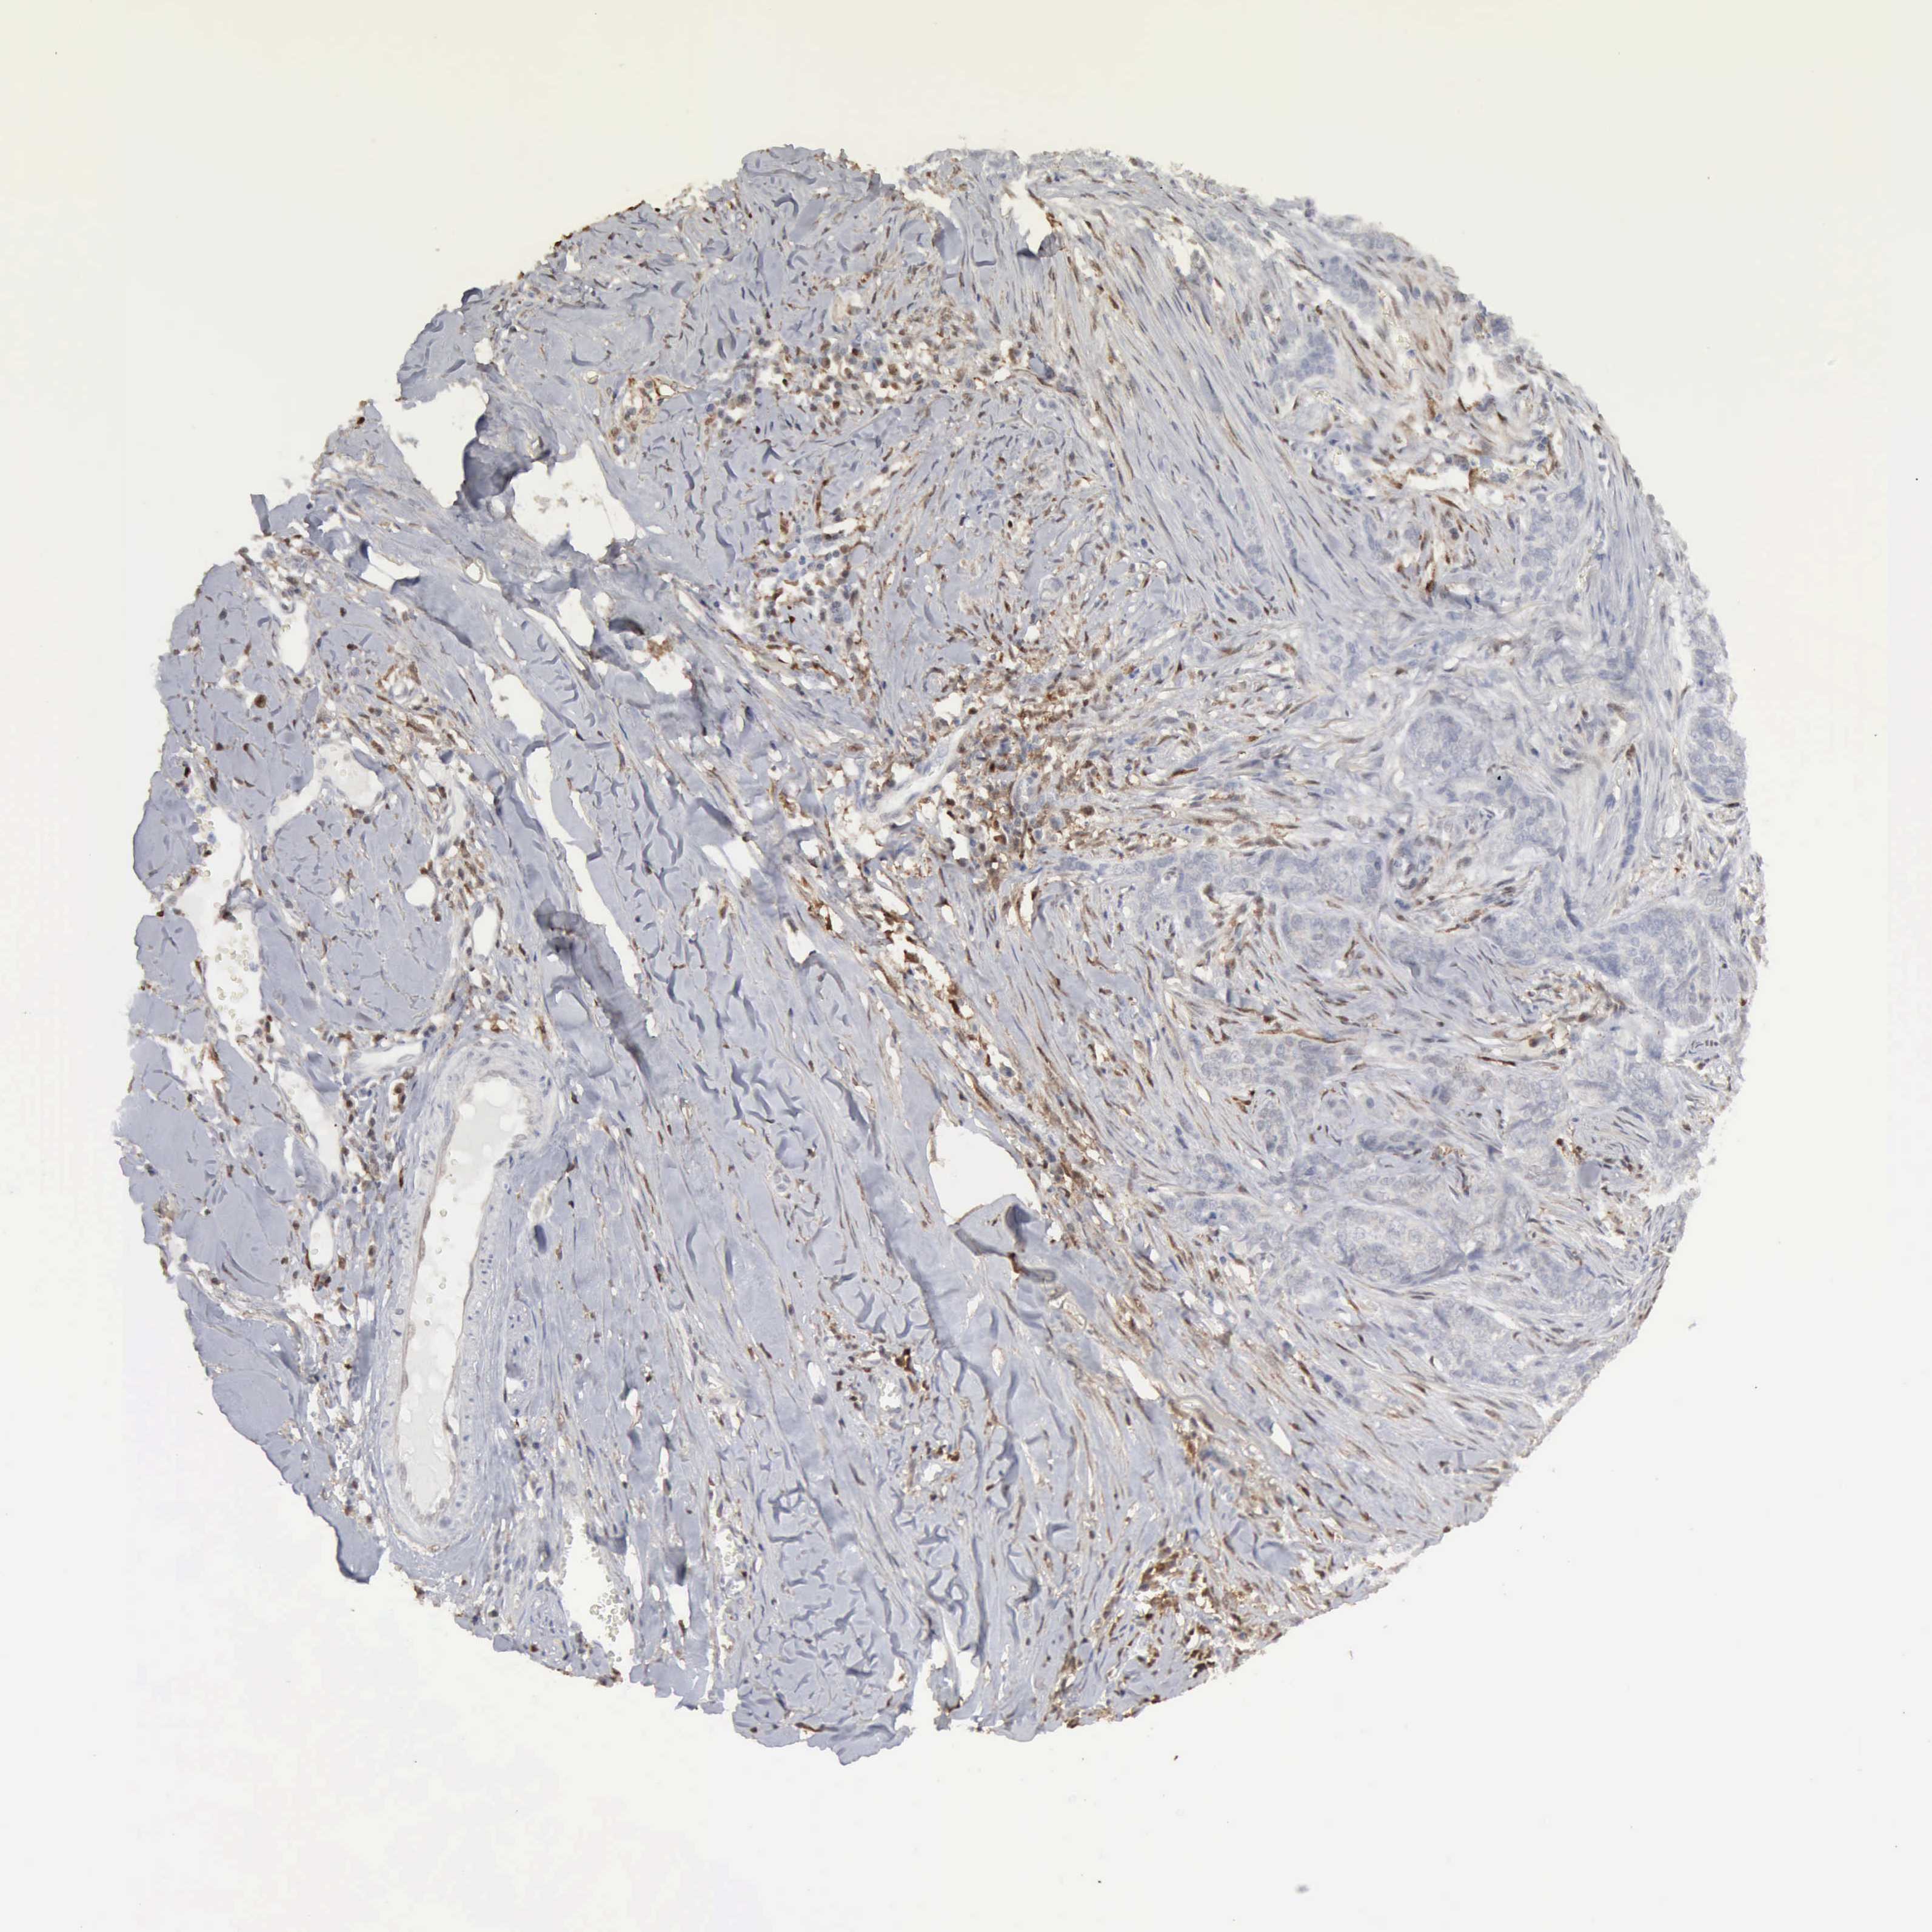

SKIN CANCER - Protein expressioni

A mouse-over function shows sample information and annotation data. Click on an image to view it in a full screen mode. Samples can be filtered based on level of antibody staining by selecting one or several of the following categories: high, medium, low and not detected. The assay and annotation is described here.

Each image is clickable and will lead to virtual microscopy that enables deeper exploration of all samples and also displays staining intensity scores, fraction scores and subcellular localization as well as patient and tissue information for each sample.

Antibody HPA000931

Staining

High

Medium

Low

Not detected

Intensity

Strong

Moderate

Weak

Negative

Quantity

>75%

75%-25%

<25%

None

Location

Nuclear

Cytoplasmic/membranous

Cytoplasmic/membranous,nuclear

Squamous cell carcinoma, NOS

Basal cell carcinoma